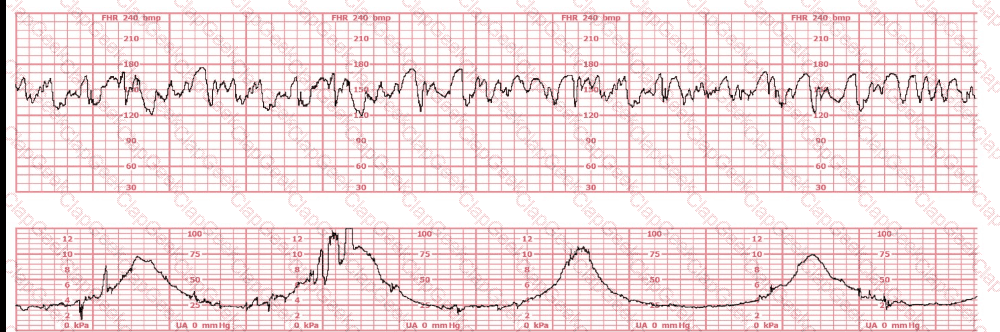

The decelerations seen in the fetal monitoring tracing shown are best described as: